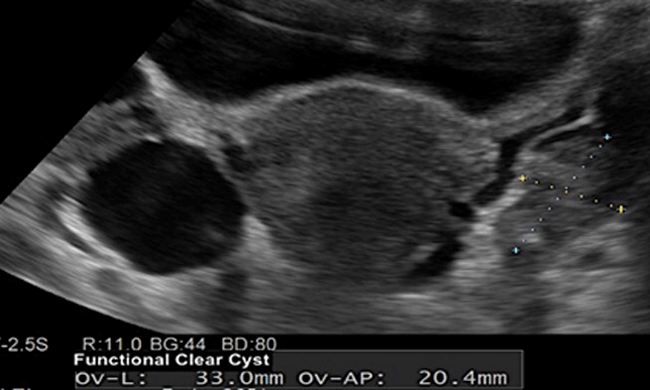

"Water Cysts" or Functional ovarian cysts are the most common cysts in the reproductive age. Functional cysts are the result of normal ovulation function. They contain only fluid and usually resolve in a month or two, hence treatment is rarely needed. They are usually less than 5cm although sometimes they can be as large as 8cm.